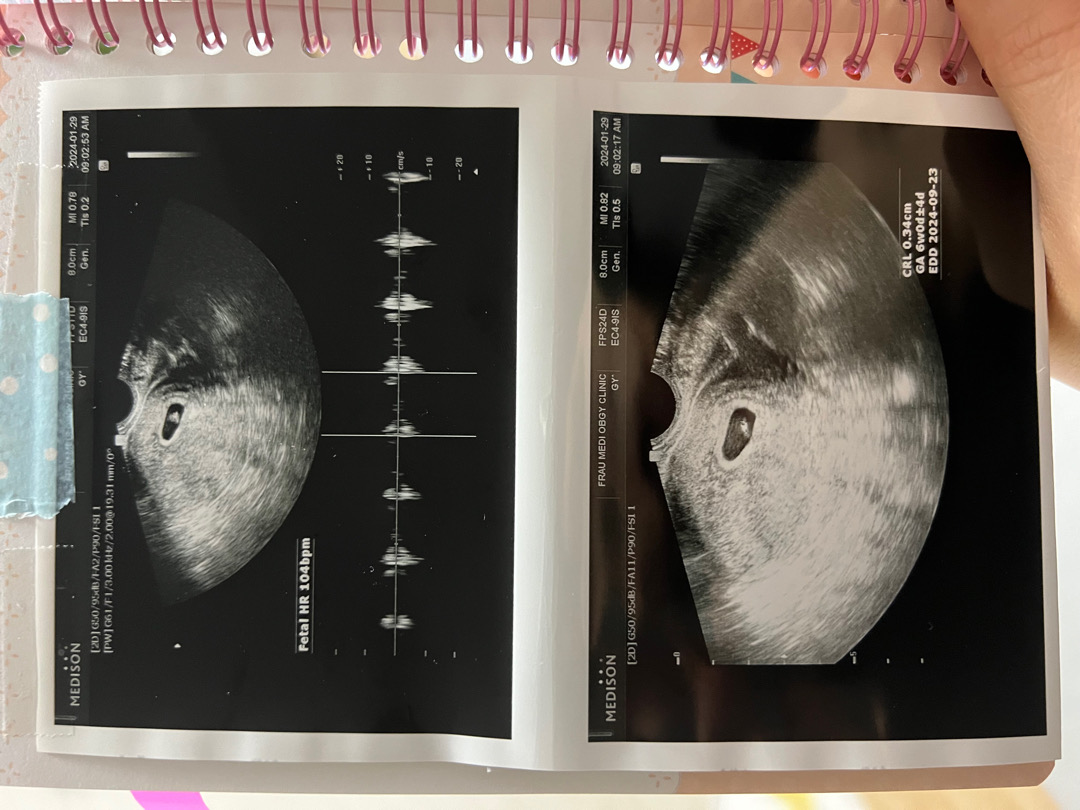

6주차에 심장소리 들었어요

4주차에는 다른병원에서 초음파 보고 5주차5일일때 궁금해서 다른병원갔더니, 6주된거 같다고 하더라고요! 기존 예정일이 9.25였는데 9.23으로 줄었어요! 104ppm 이면 괜찮은거겠죠?

저도 6주1일차에 애기3.2mm 104bpm이었어요 선생님이 그때는 100회만 넘으면 정상적이라고 하셨어요